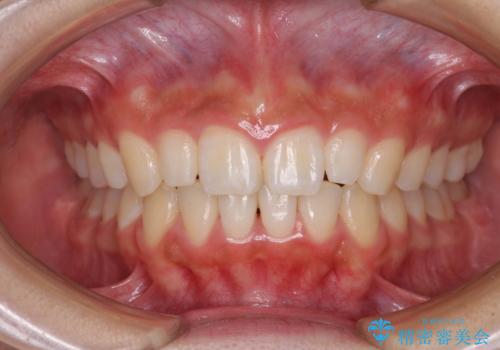

前歯のデコボコを治したい インビザラインによる矯正治療

- 前歯のデコボコ気になるとのことで来院された患者様です。

上下顎ともに歯列全体の後方移動とIPR(歯と歯の間を削る)によってデコボコが解消するように設計し、インビザラインにより治療を行うこととしました。

上顎左右前歯に矮小歯があるため、上顎の奥歯は下顎に対して相対的に前方に位置することになりました。

それでも奥歯の咬みにくさはなく、患者様には大変満足していただきました。